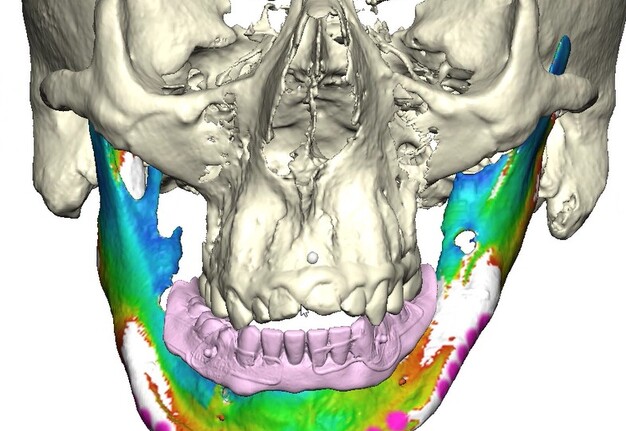

Records for this patient were collected using a dual-scan CBCT and intraoral scanning. A surgical planning session was completed with KLS Martin for the fabrication of a CAD-CAM subperiosteal implant system with immediate loading of a mandibular prototype (Figs 2-5).

A 3D-printed mandibular model with the subperiosteal system and prototype in place was also fabricated (Figs 6 and 7).

• Stereophotography scans of the cast were performed with the prototype in place and after removal with ICam4D scan bodies using Trios 4 Wireless Pod (3Shape) (Figs 12-14).